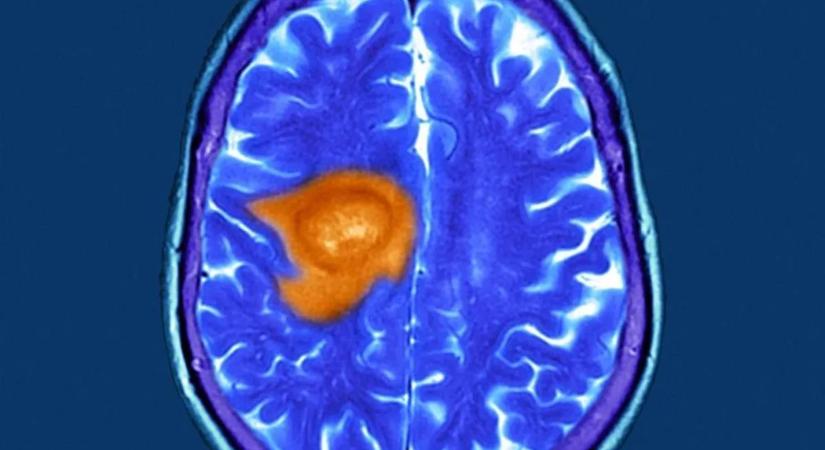

A glioblasztóma napjaink egyik legfélelmetesebb és legagresszívabb agydaganat típusa.